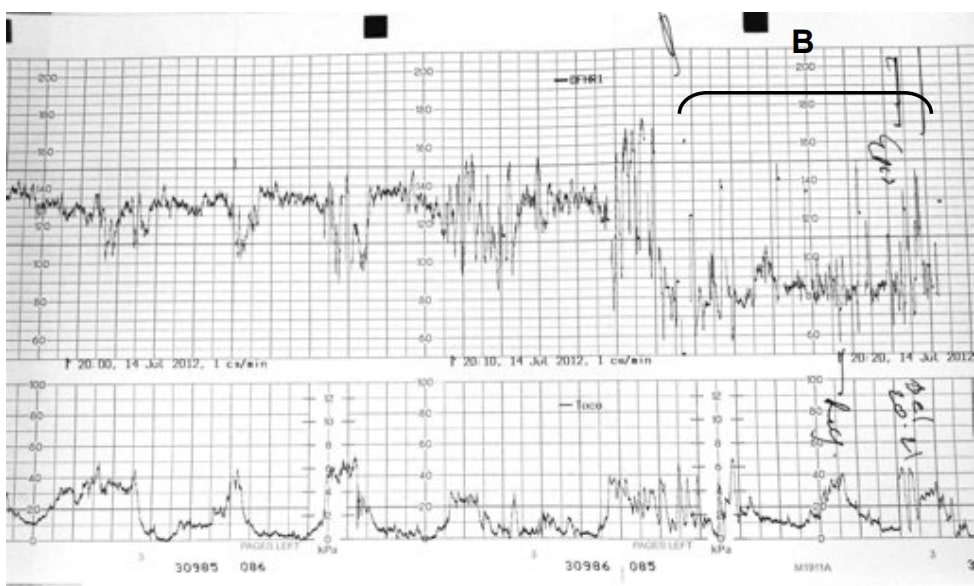

Abdominal ultrasound may be performed to estimate the gestational age and to rule out placental abruption which can complicate eclampsia. CTG monitoring is likely to indicate evidence of fetal distress and bradycardia.

Fig 2 - Cardiotocogram indicating fetal distress. Bradycardia is observed in the bracketed segment (B).

Cardiotocogram indicating fetal distress. Bradycardia is observed in the bracketed segment (B).

Eclamptic seizures are treated with magnesium sulphate (Table 4). The patient should be assessed for signs of hypermagnesaemia (hypo-reflexia, respiratory depression), and the fetus monitored via continuous CTG.

A rapid decrease in maternal blood pressure can cause fetal heart rate abnormalities. Therefore, continuous CTG monitoring is used during and for 30 minutes after giving IV anti-hypertensives.